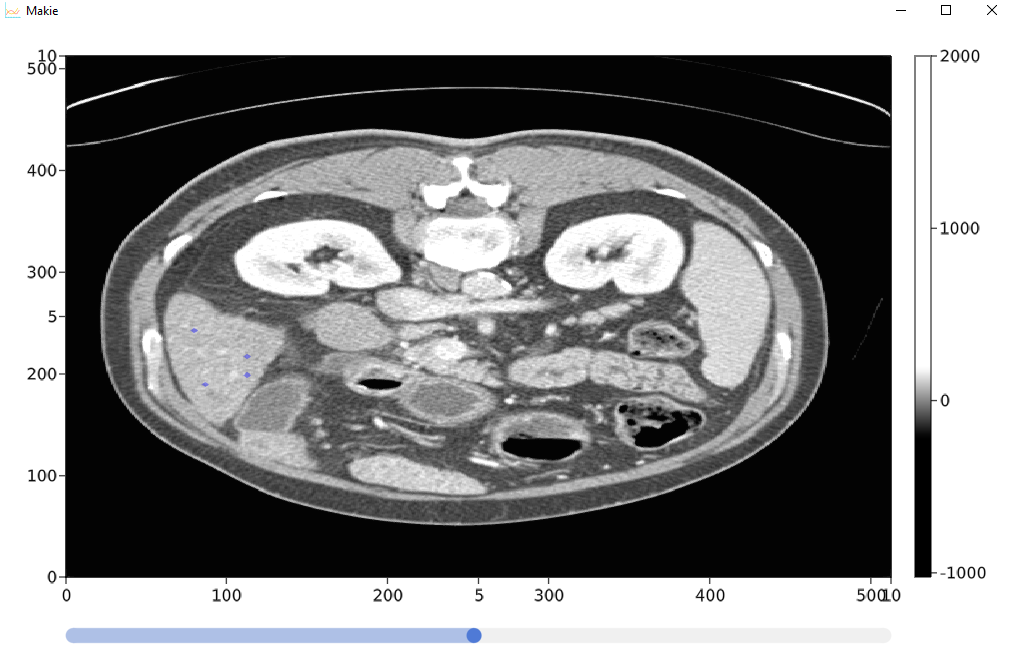

我最终完成了管理,基本上我加载了存储在hdf5中的三维数据(我使用python将它从原始的hdf5中加载到了hdf5中)。

它允许查看横向切片,并在遮罩中注释3d路径,该掩码将显示在主图像上。

MyImgeViewer.singleCtScanDisplay(arrr, maskArr,minimumm, maximumm)现在定义所需的模块

```@doc仅在横向平面上简单地显示单个图像,我们还添加了一个掩码,

代表医学图像的主要三维数据,例如CT,每个体素代表X射线衰减值。

最小值,最大值--我们可以在图像中得到的大约最小值和最大值。

function singleCtScanDisplay(arrr ::Array{Number, 3}, maskArr , minimumm, maximumm)

cmwhite = cgrad(range(RGBA(10,10,10,0.01), stop=RGBA(0,0,255,0.4), length=10000));

greyss = createMedicalImageColorSchemeB(200,-200,maximumm, minimumm )

currentSliceMain = GLMakie.@lift(arrr[:,:, convert(Int32,$sliderXVal)])

hm = GLMakie.heatmap!(ax1, currentSliceMain ,colormap = greyss)

currentSliceMask = GLMakie.@lift($maskArr[:,:, convert(Int32,$sliderXVal)])

hmB = GLMakie.heatmap!(ax1, currentSliceMask ,colormap = cmwhite)

indicatorC(ax1,imageDim,scene,maskArr,sliderXVal)

colorB = layout[1,2]= Colorbar(scene, hm)